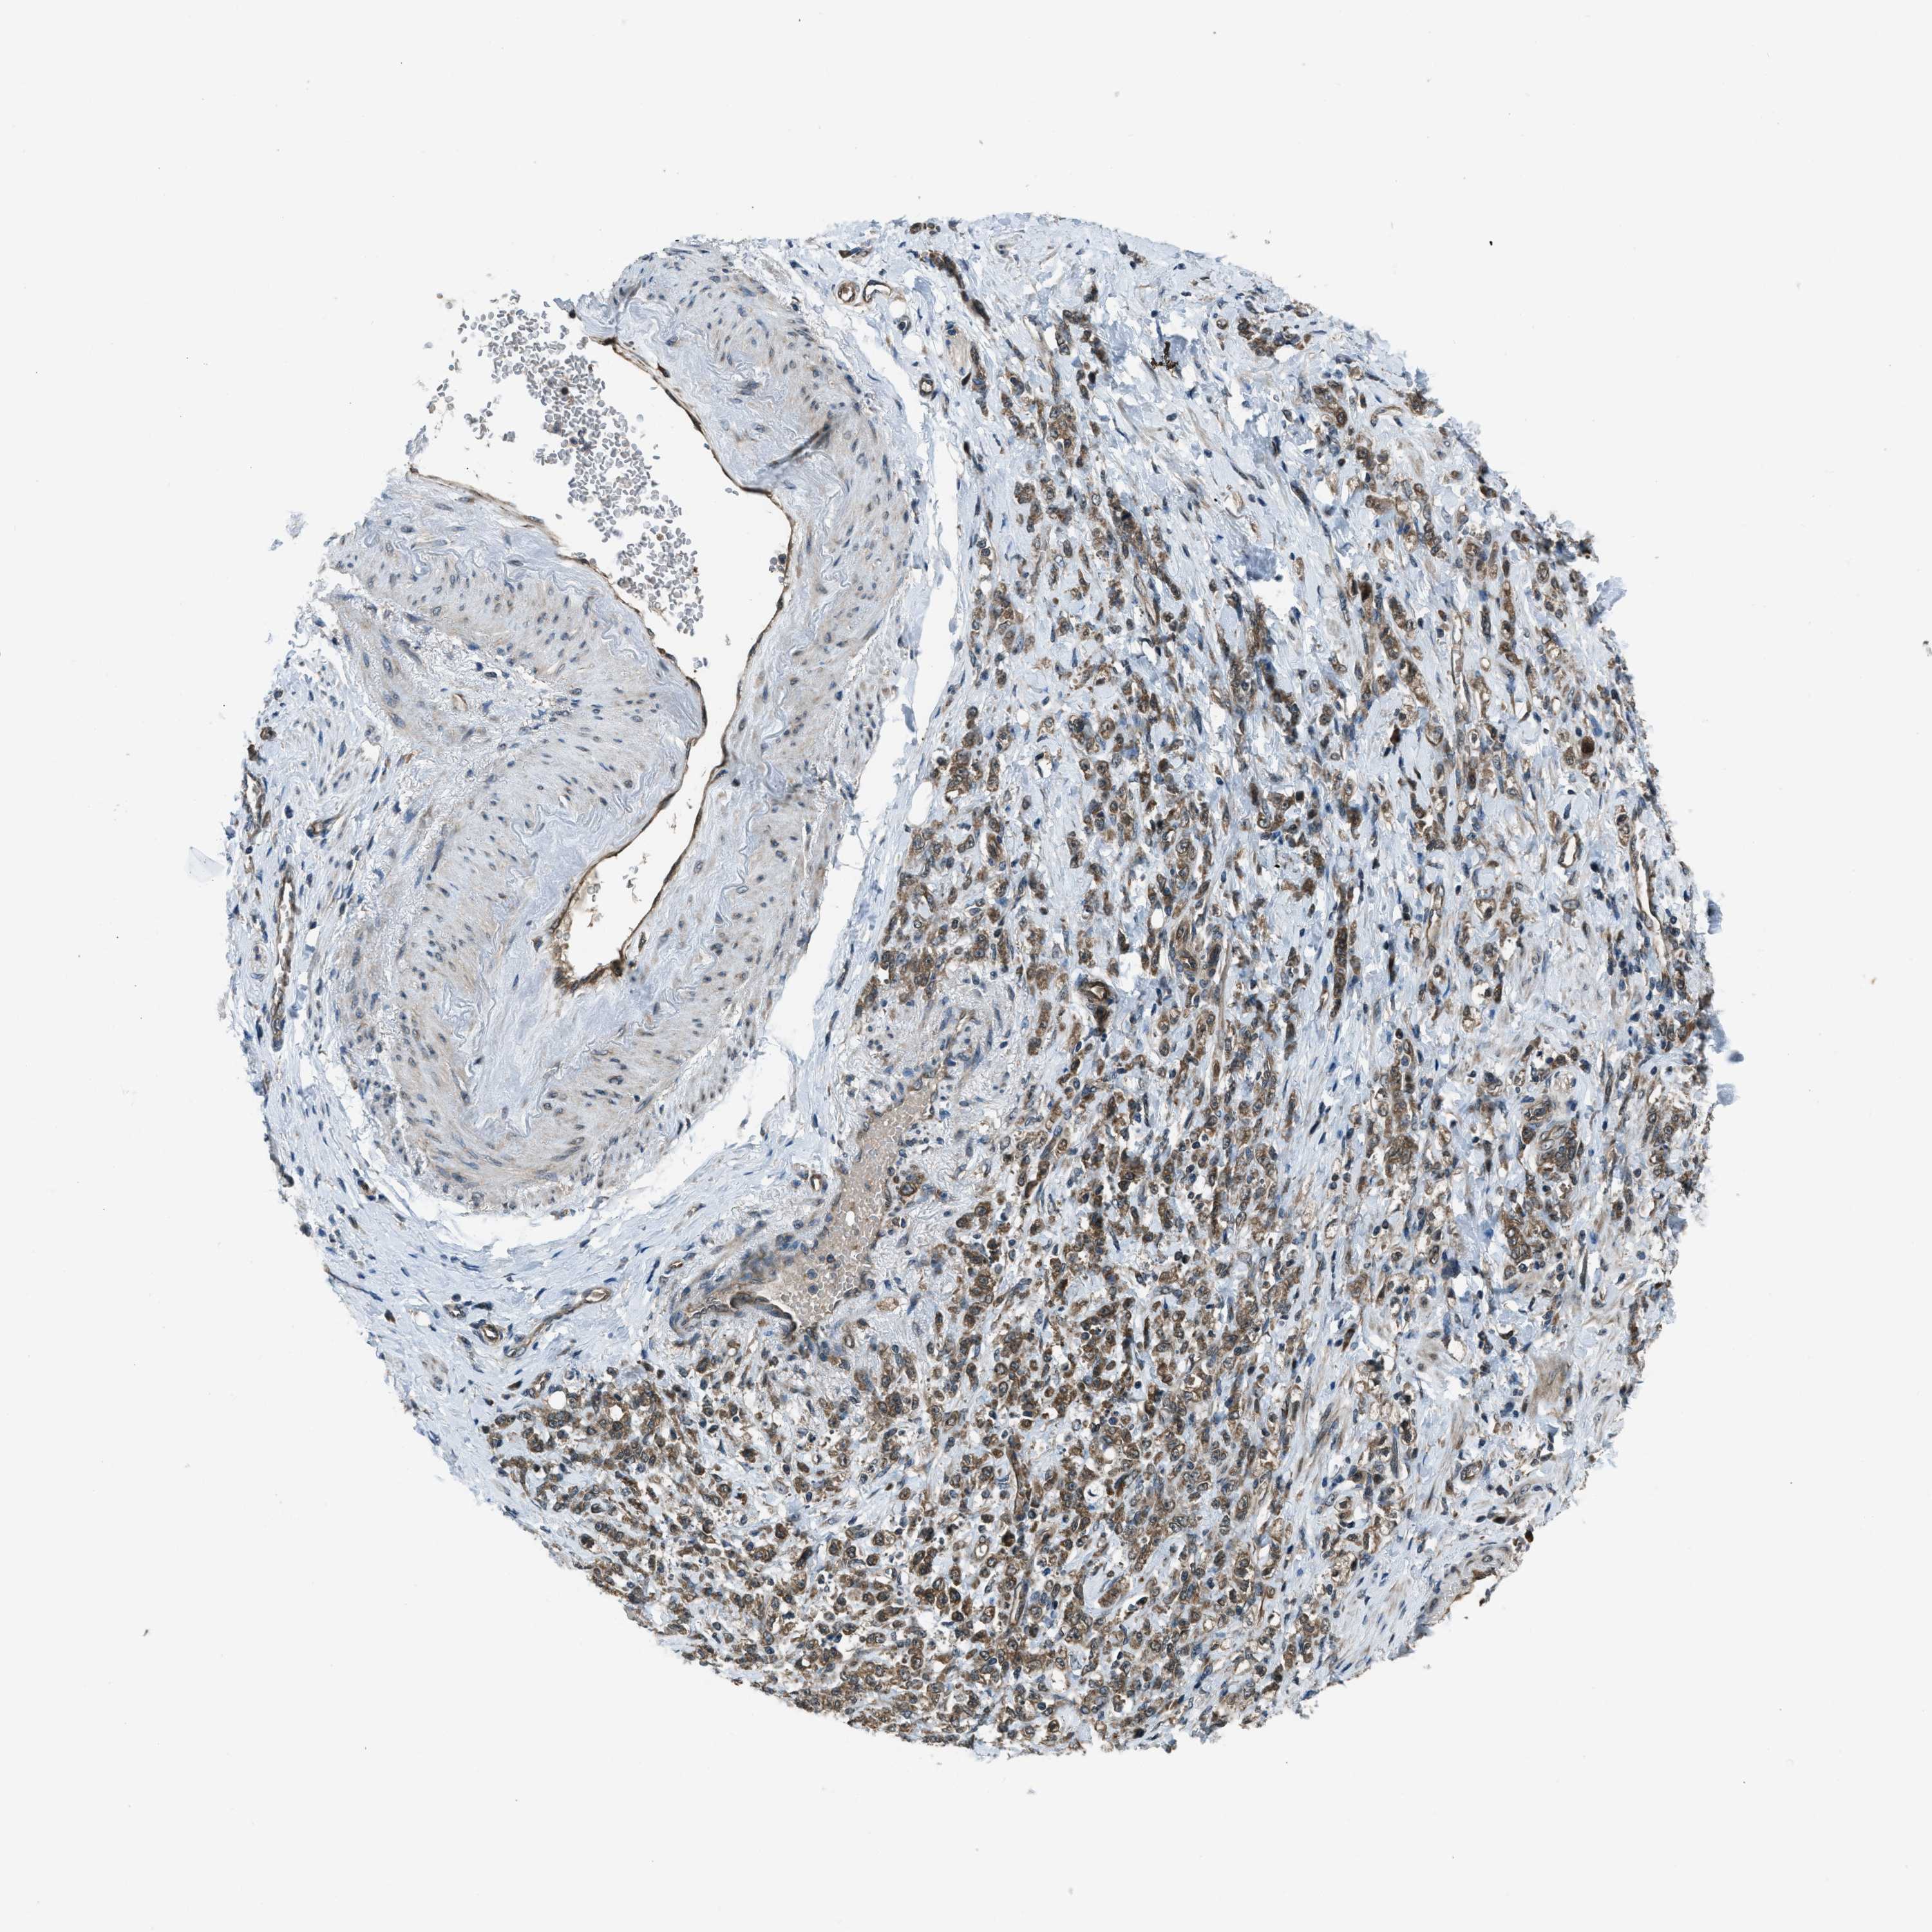

STOMACH CANCER - Protein expressioni

A mouse-over function shows sample information and annotation data. Click on an image to view it in a full screen mode. Samples can be filtered based on level of antibody staining by selecting one or several of the following categories: high, medium, low and not detected. The assay and annotation is described here.

Note that samples used for immunohistochemistry by the Human Protein Atlas do not correspond to samples in the TCGA dataset.

Antibody stainingi

Antibody staining in the annotated cell types in the current human tissue is reported as not detected, low, medium, or high, based on conventional immunohistochemistry profiling in selected tissues. This score is based on the combination of the staining intensity and fraction of stained cells.

Each image is clickable and will lead to virtual microscopy that enables deeper exploration of all samples and also displays staining intensity scores, fraction scores and subcellular localization as well as patient and tissue information for each sample.

Antibody CAB018615

Staining

High

Medium

Low

Not detected

Intensity

Strong

Moderate

Weak

Negative

Quantity

>75%

75%-25%

<25%

None

Location

Nuclear

Cytoplasmic/membranous

Cytoplasmic/membranous,nuclear

Adenocarcinoma, NOS

Adenocarcinoma, High grade